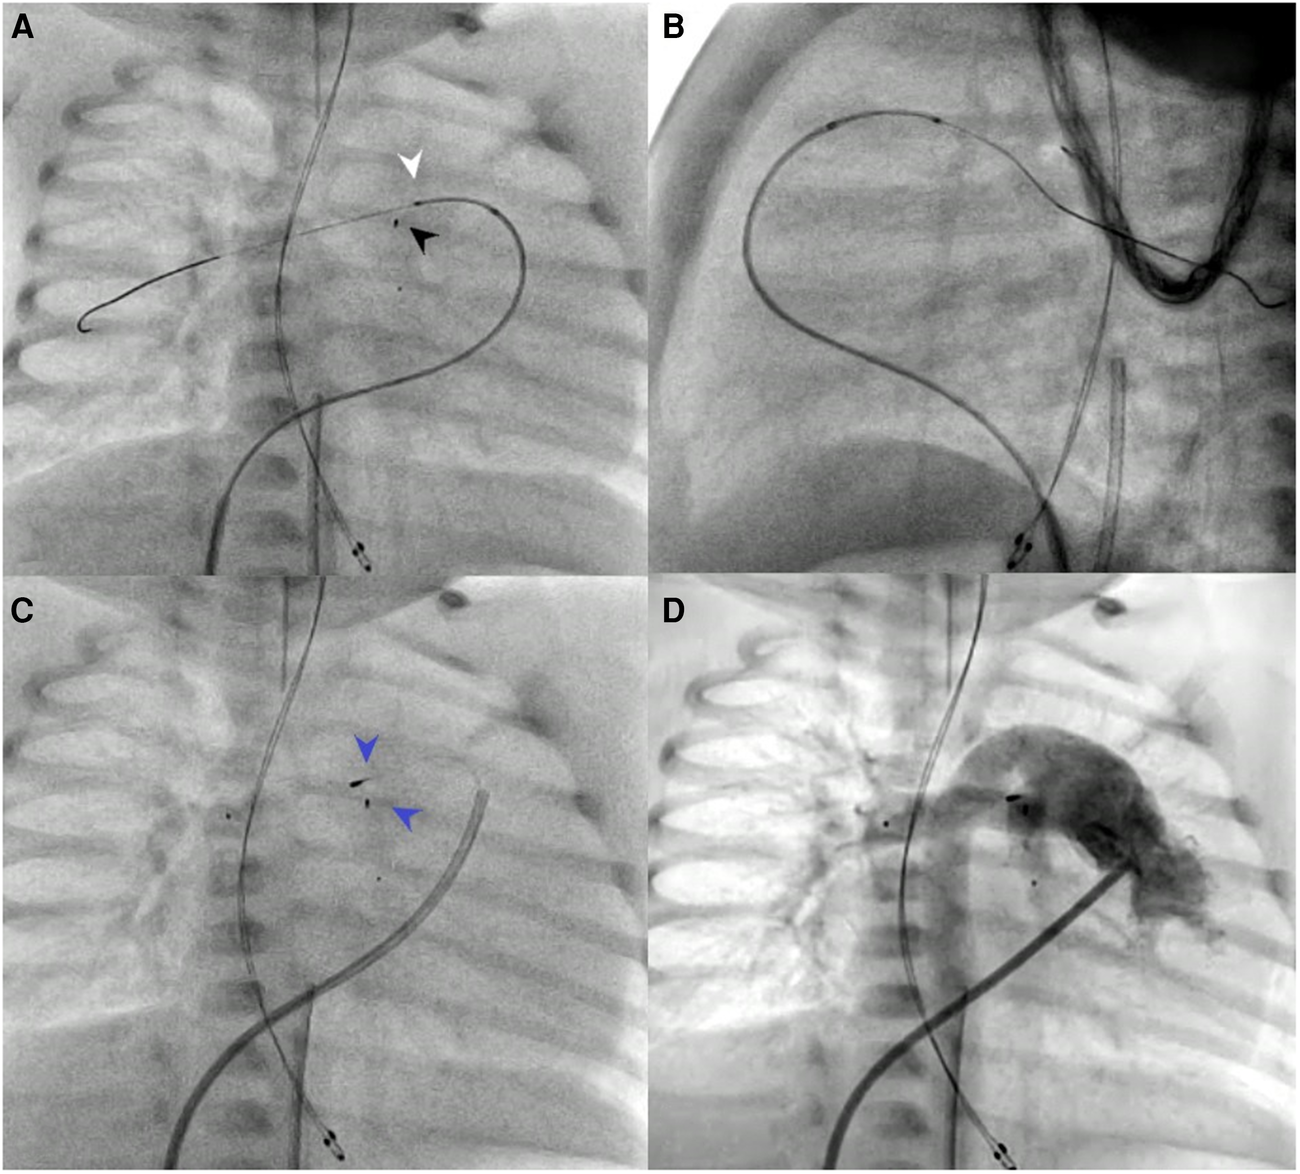

In two patients (no. 1 and no. 10) with Type II Abernathy malformations, the use of SwiftNINJA allowed us to access the acutely originating Abernathy vein from the caval vein, and also go deeper inside the liver to cannulate the best branch and rest the wire before advancing the glide over it (Figure 4). The procedure aimed to assess the patency of the portal circulation and the possibility of blocking partially the Abernathy vein to enhance the portal vein growth.

FIGURE 4

www.frontiersin.org

Figure 4. Patient no. 1 with type II abernathy malformation. The glide catheter is advanced deep inside the Abernathy vein acutely originating from the caval vein after being slid over the SwiftNINJA (A) SwiftNINJA is articulated at a 90-degree angle from the common trunk to engage deep inside the portal vein (B).